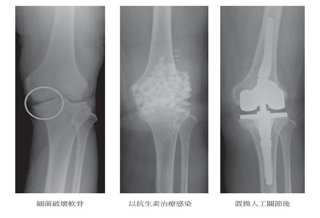

軍官O形腿 關節退化害的!

軍官O形腿 關節退化害的!#膝蓋

(優活健康網記者徐平/綜合報導)85歲許老先生為職業軍官退伍,長年飽受膝痛所苦,連腳踏車都無法騎,前幾年不僅無法上下樓梯,走路也開始出現「0形腿」,吃止痛藥不見效,3年前因寸步難行就醫,剛開始打玻尿酸稍有改善,但不到半年膝蓋又開始疼痛,後來接受「機器人手臂膝關節置換術」,術後立即可以下床,隔日就出院,2周後就騎著單車趴趴走,甚至到澳洲爬山。每10個老年人 有7個受膝關節炎之苦老年人膝蓋問題雖不會馬上致命,卻會慢性影響生活品質,並與失智、中風和冠狀心臟病並列為造成老人失能的前4大疾病,據統計,台灣每10個70歲以上老年人,就有7個飽受退化性膝關節炎之苦,帶來疼痛與腿部關節活動的限制,嚴重者甚至無法行走、只能以輪椅代步。台北中山醫院骨科吳濬哲醫師表示,「退化性膝關節炎」是關節軟骨經過多年的使用,造成軟骨磨損、滑囊發炎及增生,高達85%的患者膝關節疼痛,問診後發現超過90%患者會自行吃止痛藥,另外也有超過50%成老人家,誤以為補鈣可以改善退化性膝關節炎。機器人手臂膝關節置換術 降軟組織破壞吳濬哲醫師表示,許多退化性膝關節炎患者擔心「傳統全人工膝關節置換術」的手術傷口大、開刀危險性高,加上顧慮術後會增加子女或家人照顧的負擔而選擇放棄手術,而目前「機器人手臂膝關節置換術」只針對部分磨損、壞損的關節做磨除,保留健康的骨頭、前後十字韌帶及本位感神經組織,大幅降低傷口周圍的肌肉及軟組織拉扯和破壞。